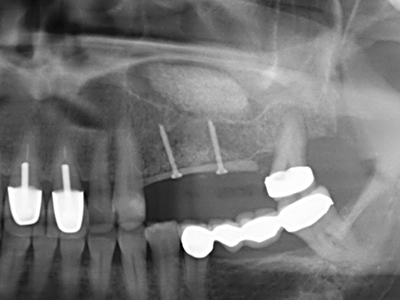

Sollen chirurgische Eingriffe mit unmittelbarer Knochenbeziehung an empfindlichen Strukturen wie Blutgefäßen oder Nerven erfolgen, so bergen rotierende Instrumente ein erhebliches Potential an iatrogener Schädigung. Gerade bei Nervdarstellungen nach iatrogener Schädigung, oder aber im Zuge einer Nervlateralisation für resektive und rekonstruktive Eingriffe oder Implantatinsertionen können piezoelektronische Geräte hilfreich sein Knochendeckel zu präparieren und nervnahe Hartgewebsanteile zu entfernen (Abb. 17-20). Ein leichter Kontakt des Nervstrangs zur Piezospitze bleibt dabei in der Regel folgenlos – allerdings kann eine unvorsichtige Vorgehensweise mit sägeartigen Bewegungen bzw. Ansätzen bei noch vorhandener knöcherner Unterlage durchaus temporäre oder aber auch permanente Nervschädigungen verursachen. Das Risiko einer solchen Schädigung wird jedoch als wesentliche geringer eingeschätzt als unter Anwendung von Säge- oder Fräsinstrumenten (Pereira, Gealh et al. 2014).

Wie sich in der Vergangenheit gezeigt hat stellt prinzipiell jeder knochenchirurgische Eingriff eine mögliche Indikation für die Piezochirurgie dar. So lässt sich die Präparation des mobilen Segmentes bei der Distraktionsosteogenese (Abb. 23-25) und der Sandwichosteotomie mit speziellen Ansätzen bewerkstelligen, ohne die für den Erfolg beider Techniken essenzielle Blutversorgung des krestalen Anteils zu gefährden (Gonzalez-Garcia, Diniz-Freitas et al. 2008).

Für die Entnahme von Implantaten ist die Präparation eines vestibulären Knochendeckels möglich, der nach Entfernung der Implantatschraube refixiert wird und auf diesem Wege die Kontur des Alveolarfortsatzes erhält.

Weitere Einsatzgebiete ergeben sich in der Kieferhöhlenchirurgie: Hier können nach konzentrischer Präparation eines in der Regel trapezförmigen Knochendeckels der fazialen Kieferhöhlenwand Pathologien und Fremdkörper aus der Kieferhöhle entfernt werden. Der Knochendeckel wird nach Abschluss des intra-antralen Operationsanteils reponiert und durch Verkeilen oder adaptierende Nähte gegen Dislokation gesichert.